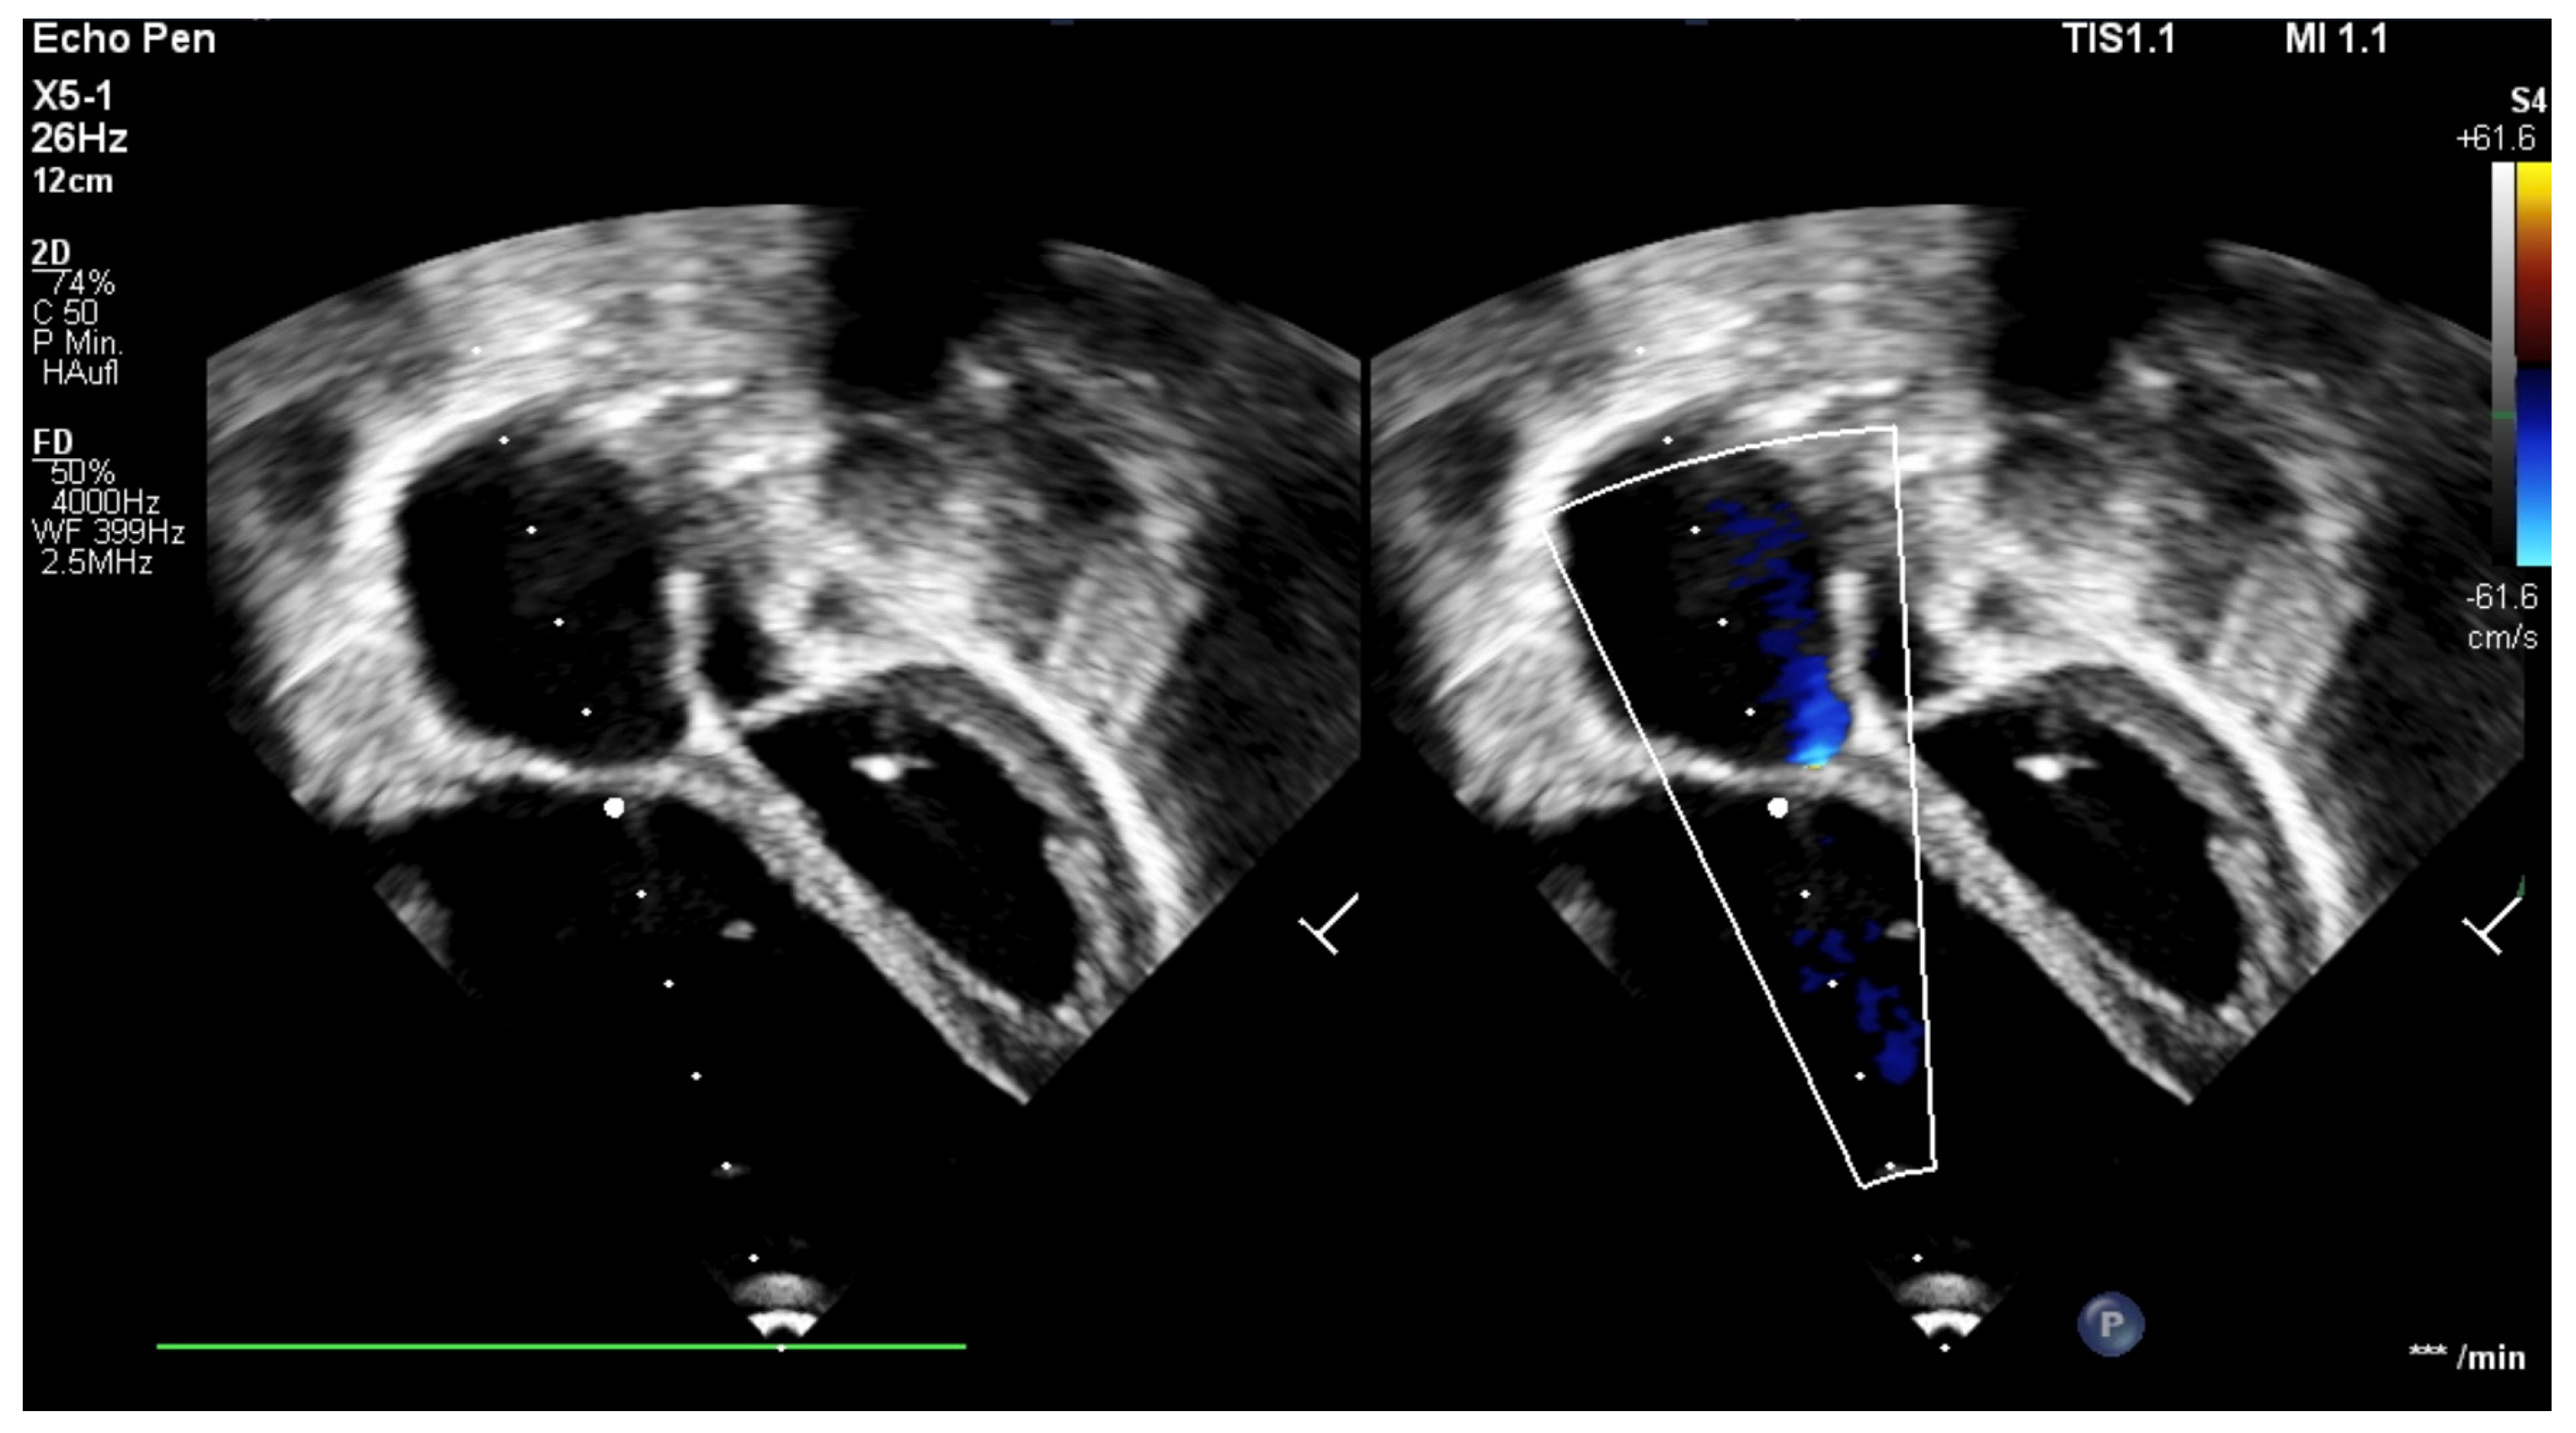

Figure 2. Echocardiography, four-chamber view; (a) the apical displacement of the tricuspid valve; (b) color-flow Doppler showing severe tricuspid regurgitation; immediately postpartum.

The patient was born late-preterm by cesarean section (36 + 3 weeks’ gestation, birth weight 2400 g, APGAR 6/9/9, umbilical cord pH = 7.38) with prenatally diagnosed EA; we started immediate, uncomplicated primary care with CPAP respiratory support, umbilical vein catheter and prostaglandin E (PGE) infusion for ductus-dependent lung perfusion. With stable hemodynamics, the neonate was transferred to our pediatric cardiac intensive care unit (pCICU). At admission, the patient exhibited independent feeding ability, a heart rate of 150 bpm, pre- and postductal oxygen saturation was >85%, and additional oxygen was required until the third day of life. ECG showed sinus rhythm with P-dextroatriale, QRS of approx. 80 ms, and no arrhythmia. On the second day postpartum, Troponin I and proBNP were measured as 9 pg/mL and 27,065 ng/L, respectively. Mild signs of heart failure were treated with diuretics. Echocardiography confirmed severe EA, consistent with Carpentier type C, with RA/(RV + LA + LV) > 1 (RA = right atrium; LA = left atrium), ASD type II of 10 mm, and the prolapse of the anterior leaflet of the TV into the RVOT leading to severe insufficiency with a coaptation defect and a V. contracta of 1.2 cm. Additionally, membranous pulmonary atresia with preserved confluence was found. The pulmonary arteries (PAs) were hypoplastic, with left PA (LPA) = 2.7 mm (z = −2.3) and right PA (RPA) = 3.2 mm (z = −1.7). The left-sided heart segments did not show any malformation, insufficiency, or stenosis, and their function was deemed to be satisfactory (fractional shortening (FS) = 22.6%; see Figure 1 and Figure 2, Supplementary Materials, Figure S1).